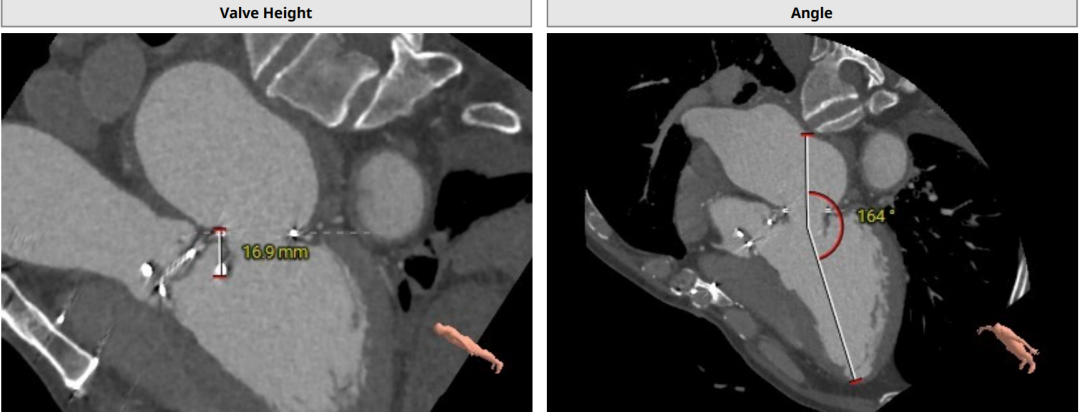

CT分析